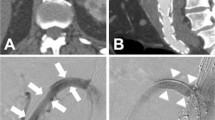

Details of the surgical technique for open repair of TAAAs at our institution have been previously described [12]. The strategy for VV revascularization was customized (Fig. 20.1) according to the following principles: Inclusion in a “beveled” aortic anastomosis or in Carrel patch was favored in case of short distance between the VV ostia; when the aneurysm included the visceral aortic segment, no more than three VVs were normally reimplanted together in a single Carrel patch to avoid the risk of late aneurysm recurrence [16]. A VV originating far from the others was usually reconstructed separately by direct reimplantation on the main aortic graft or by individual graft interposition (6-mm heparin-bonded Dacron or ePTFE). Since 2012, the Gore Hybrid Vascular Graft (W.L. Gore and Associates, Flagstaff, AZ) has been selectively used to perform separate revascularization of one or two VVs allowing for distal sutureless anastomosis. The specific operative technique for this device has been previously described in detail [12]. A separate revascularization of all VVs has always been preferred—in most cases accomplished with presewn multibranched grafts (Coselli graft, Vascutek Terumo, Renfrewshire, UK, or Hemashield Platinum TAAA graft, Maquet, Sunderland, UK)—in case of large aneurysms with excessive distance between all VV ostia, in the event of recurrent aneurysmal disease after previous TAAA surgery, or in patients affected by connective tissue disorders.

Intraoperative views of different techniques for VV reconstruction: (a) Carrel patch including CT (C), SMA (M), and RRA (R). (b) Direct reimplantation of the LRA on the main aortic graft. (c) Revascularization of all VVs using a presewn multibranched graft. (d) Bilateral renal artery revascularization using two Gore Hybrid Vascular Grafts with sutureless distal anastomosis